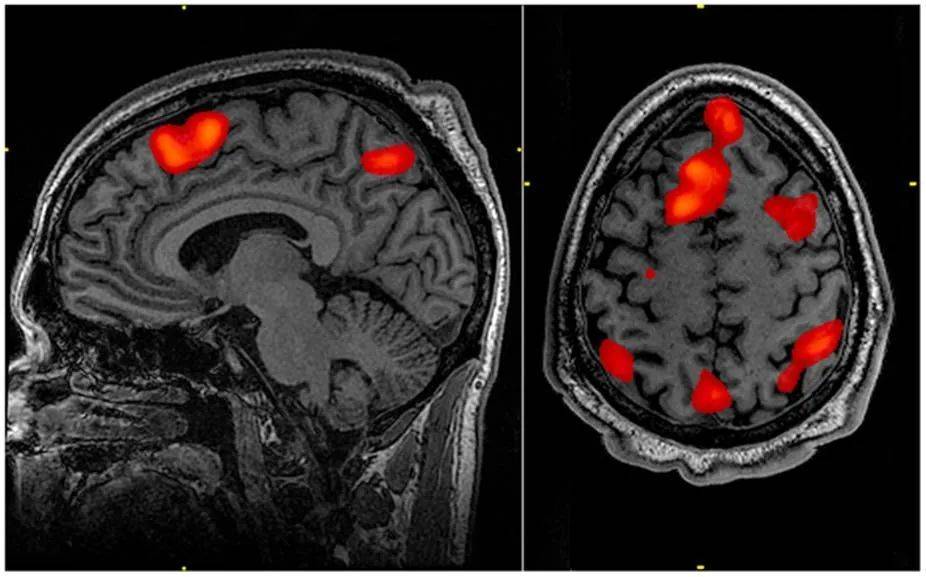

目前,ASMR领域仅有少数几个脑成像研究,其中一项研究应用功能性磁共振成像(fMRI)技术监测局部脑活动,实时检测观看ASMR视频的受试者在感受到ASMR过程中,大脑发生了什么变化。

功能性磁共振成像扫描图

图片来源:John Graner/wikipedia

视频内容包括了目前受欢迎程度较高的几类:轻拍声、耳语、沙沙声、重复任务等。观看过程中,受试者需要按三个按钮:处于正常状态就按“基线”按钮;处于放松愉悦的状态就按“放松”按钮;感受到ASMR带来的身体酥麻感就按“酥麻”(tingle)按钮。

结果显示,当受试者按了“放松”按钮时,除了听觉视觉皮层被激活,内侧前额叶皮质(mPFC)也被激活了——mPFC与自我意识,社交认知以及社交行为相关联,这说明ASMR视频可以像实际的社交活动一样激活大脑。有趣的是,当受试者按了“酥麻”按钮时,大脑中负责奖赏以及情绪唤起的脑区被激活了,包括伏隔核(NAcc)、背侧前扣带皮层(dACC)和岛叶与下额回之间的双侧区域(insula / IFG),简单来说,当你体验ASMR觉得头皮有酥酥麻麻的感觉时,大脑也感受到了快乐。